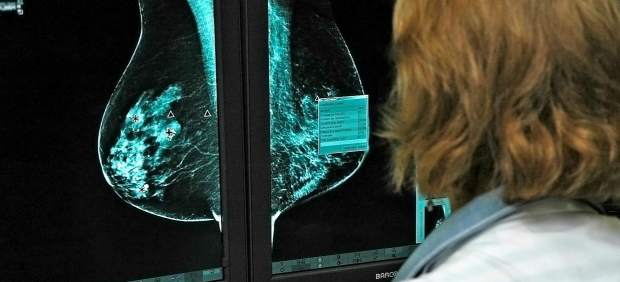

Investigación sobre el cáncer de mama

Investigadores españoles han descubierto un tipo de células inmunitarias que predicen la respuesta al tratamiento de las pacientes con el cáncer de mama más agresivo.

La investigación, que publica la revista “Clinical Cancer Research”, ha certificado la importancia de estas células, un tipo concreto de linfocito, en el éxito de los tratamientos antitumorales en pacientes con cáncer de mama HER2 positivo.